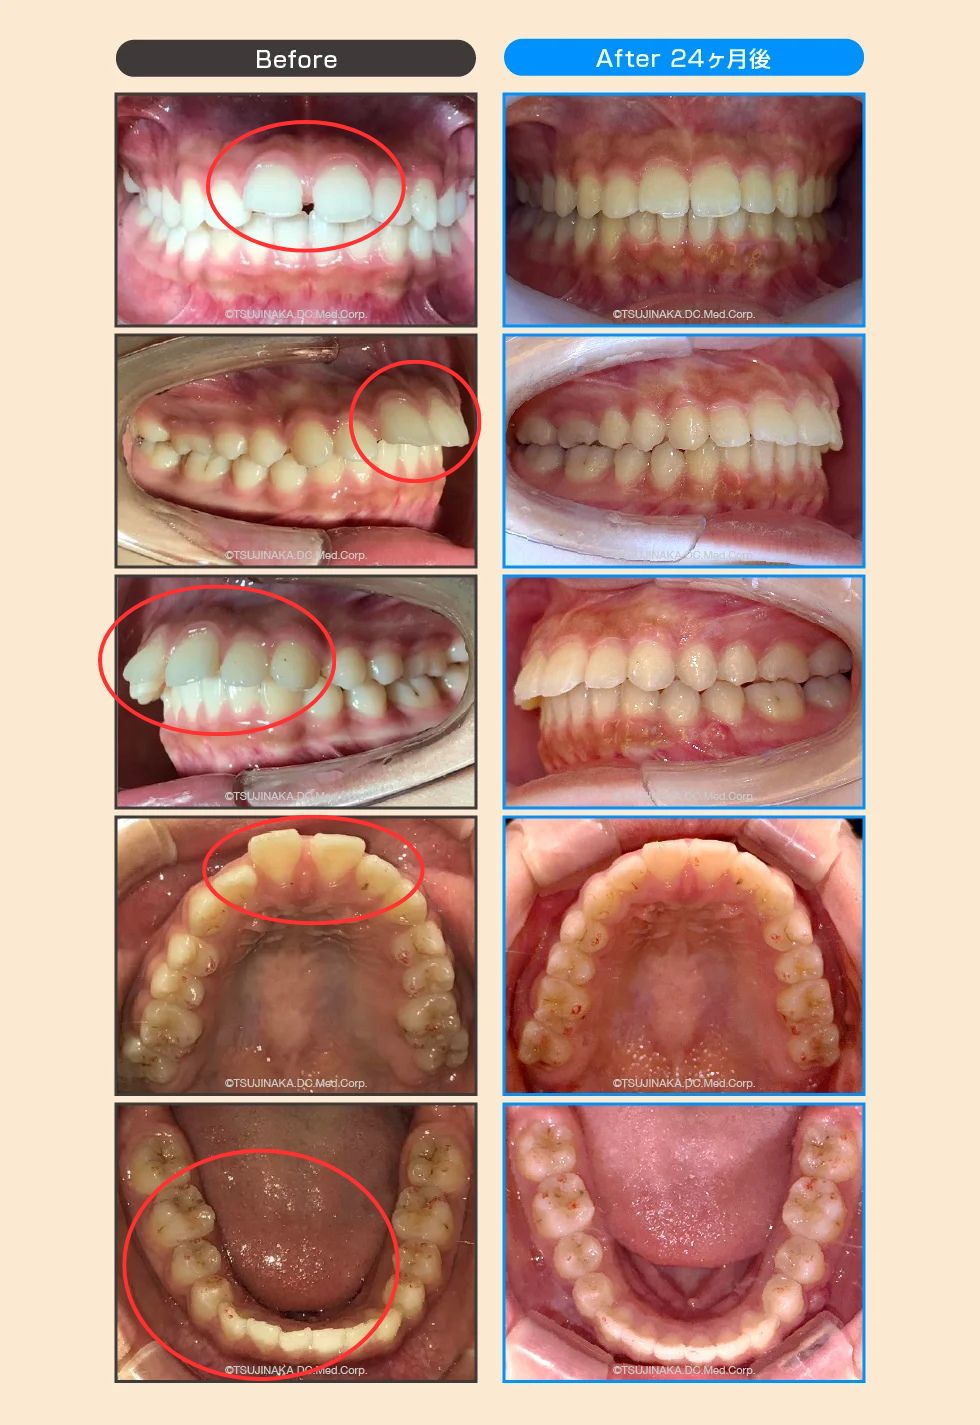

【症例No.7345】小学校の頃から歯が前に出ているのとすきっ歯が気になっていた

小学校の頃から歯が前に出ているのとすきっ歯が気になっていた

前歯のすき間や前歯が出ていることが気になるとのことでご相談いただきました。マウスピース型矯正装置を用いた矯正治療を行い、必要に応じて顎間ゴム(ゴム掛け)を併用しながら、歯列・咬合関係の改善を目指しました。

| 主訴 | 前歯のすき間(すきっ歯)と前歯が出ていることが気になる |

| 診断名 | 歯間離開(正中離開)/上顎前突/下顎叢生 |

| 治療期間 | 2年(※個人差あり) |

| 通院回数 | 14回 |

| 費用 | 80万円(税込・自由診療) |